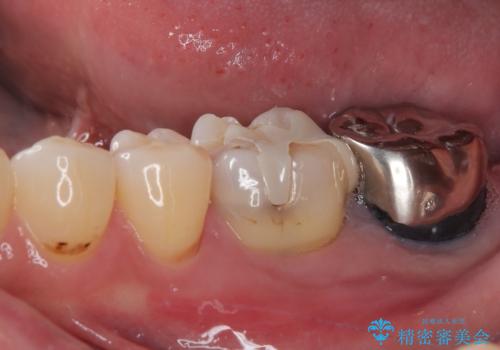

- 下顎大臼歯が噛めないほどの痛みを感じるとのことで来院された患者様です。

レントゲン写真などで診査を行ったところ、不適合な詰め物の周りから炎症が波及し、神経組織が壊死していると診断されました。

まずは根管治療を行い、症状が消退したことを確認してオールセラミッククラウンにて補綴治療を行うこととしました。